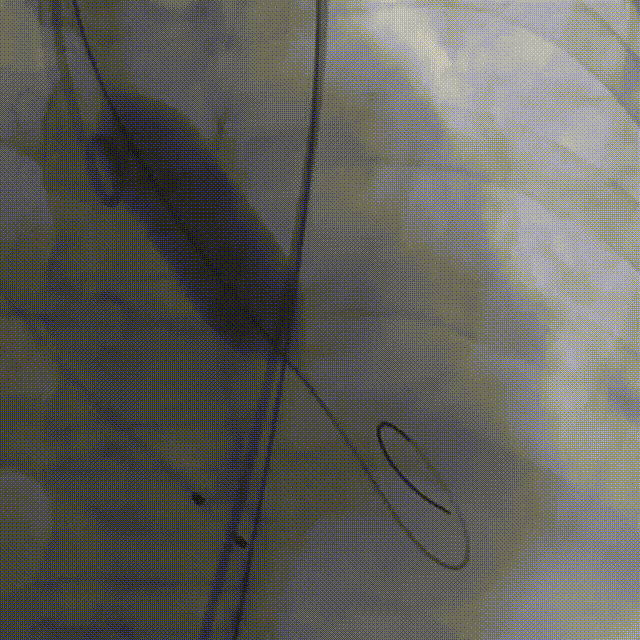

12.术后造影

术前压差103mmHg

术后压差2mmHg

术后一周复查超声平均压差是11mmHg,无瓣周漏,瓣膜正常工作。

近日CT复查,瓣膜形态良好无移位瓣膜正常工作,冠脉支架无异常,冠脉灌注良好。